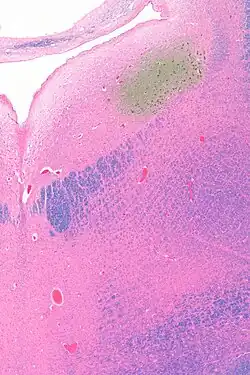

Micrograph showing the locus coeruleus (upper-right of image) in an axial section of the pons. The fourth ventricle (quasi-triangular white area) is in the upper-left of the image. The midline is seen on the left. The large white area in the upper-left corner is where the cerebellum would be. HE-LFB stain.

The locus coeruleus (LC) is located in the posterior area of the rostral pons in the lateral floor of the fourth ventricle. It is composed of mostly medium-size neurons. Melanin granules inside the neurons contribute to its blue colour. Thus, it is also known as the blue nucleus, or the nucleus pigmentosus pontis (heavily pigmented pontine nucleus).[5] The neuromelanin is formed by the polymerization of norepinephrine and is analogous to the black dopamine-based neuromelanin in the substantia nigra.